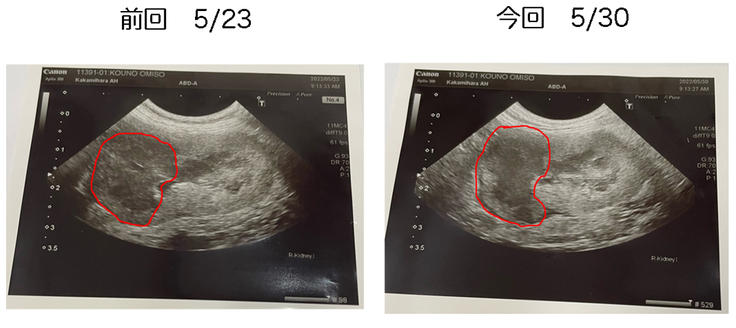

肝心の腫瘍の方は、やはり前回に投与出来なかった反動で、エコー画像の上方向に少しふくらみが見られました。しかしながら。それ程大きくも小さくもなっていない様で、とりあえずは一安心といった所です。